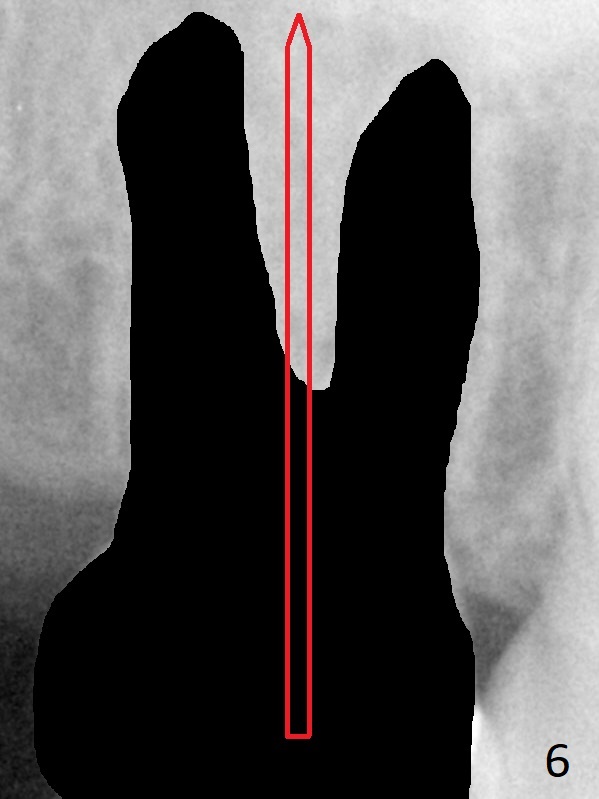

A 58-year-old woman has had RCT done at #2 for several years. The roots are trifurcated with sufficient bone height (Fig.1-3). Recently the tooth becomes symptomatic with formation of a distal fistula (Fig.4). After extraction, the septum (Fig.5 S) may be wide enough for initial drill (Fig.6). If not, resection the thin part of the septum (Fig.7 red line, with small or medium Rongeur) and use the initial drill (Fig.8). Anyway, take PA immediately to avoid sinus membrane perforation. If possible, adopt single drill technique.